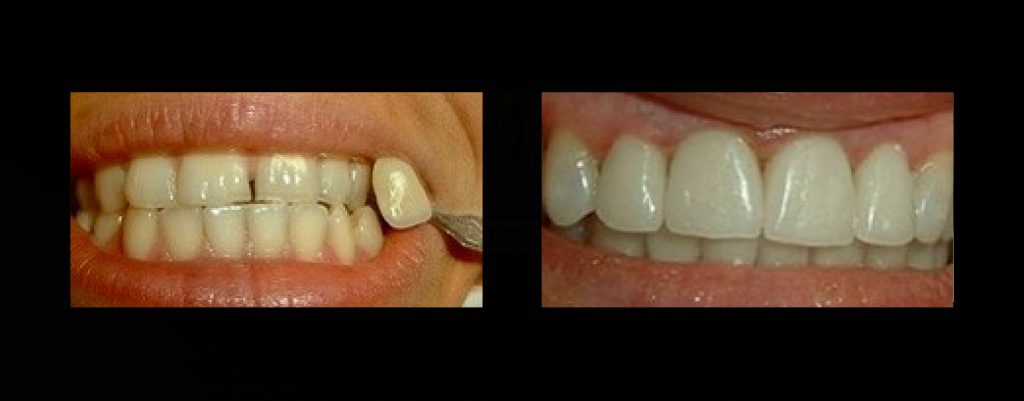

Case Study: Porcelain Veneers & Crowns

Our porcelain veneers and crowns are designed to correct a wide range of dental concerns — from discoloration and staining to chips, gaps, and uneven teeth. Each case is unique, but the results are always the same: a natural, radiant, and confident smile.

Before: Patients came to us with stained, worn, or misaligned teeth that affected their confidence and ability to smile freely.

Treatment: Using advanced digital smile design, we crafted custom porcelain veneers and crowns tailored to each patient’s facial features and expectations.

After: Bright, even, and youthful smiles that look natural and restore self-confidence in both personal and professional life.